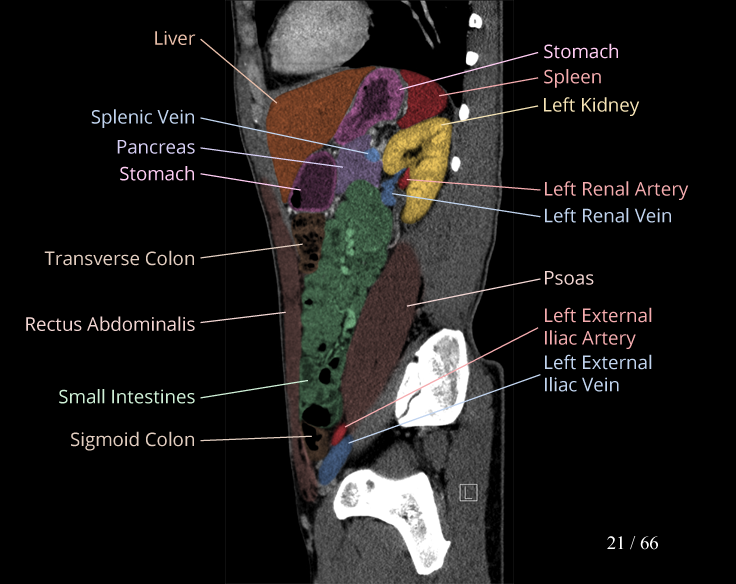

Body

Covers abdominal CT anatomy.